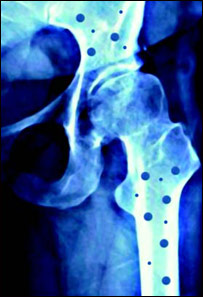

اين بيماری بيشتر استخوان های ران ها، بند های دست، ستون فقرات ومهرهای گردن را تحت فشار می آورده آنهارا می شکند.

وقتی استخوان وجود بنابر کدام دليل بشکند، بعد از گرفتن عکس (اکسری) واضيع می شود که استخوان ها شکننده شده و به بيماری نرمش يا پوکی گرفتار اند .